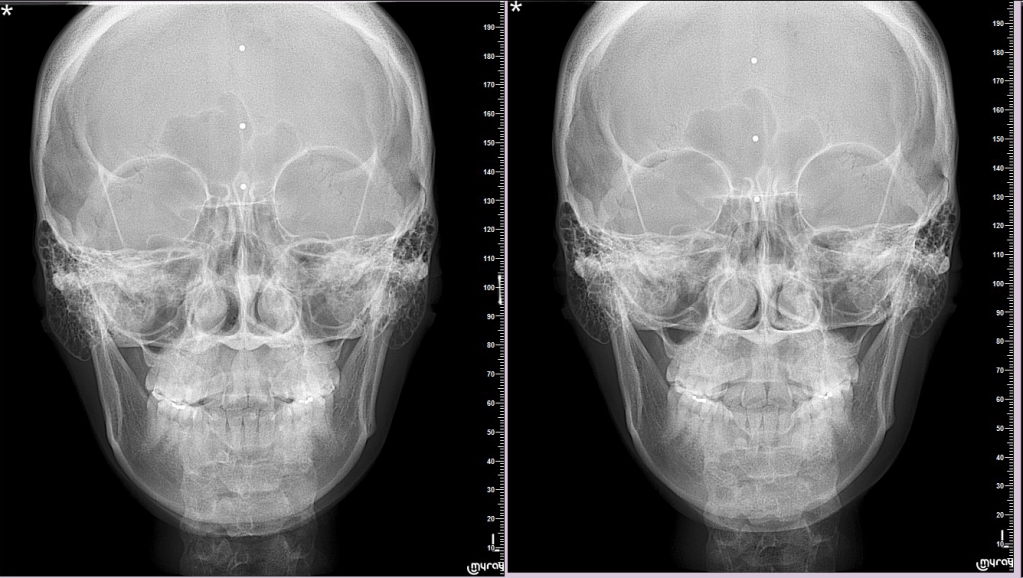

牙弓窄除了是牙齒排列不好看的原因,同時過窄的牙弓也就是代表較小的鼻腔空間,過窄的牙弓也不利于舌頭在口腔的位置,舌頭往後擠,減少呼吸道的空間,也會影響睡眠打呼,甚至呼吸中止症。

更進一步說,口腔鼻腔就像是一樓二樓的關係,口腔是一樓,上顎就是一樓的天花板,一樓天花板窄,就是二樓地板窄,當然二樓這個鼻腔房間一定窄,鼻腔窄,不能好好呼吸,怎會健康?這個想法就是說,擴了上顎牙弓,同時也擴了鼻腔空間,呼吸更順暢,就人的健康來說,比起排列美不美觀更重要,不是嗎?